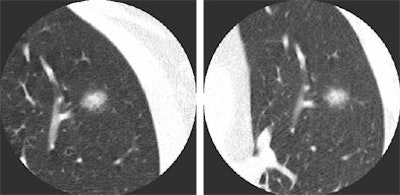

| Non-solid nodule at baseline (left) and follow-up (right). |